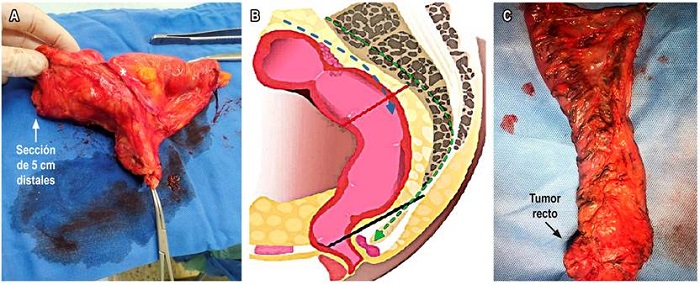

La cirugía ya no se define en términos de resección anterior, resección anterior baja o resección anterior ultrabaja. Actualmente se describe en términos de TME para tumores del tercio inferior, algunos del tercio medio con compromiso extraperitoneal y escisión mesorrectal específica o escisión parcial del mesorrecto (pME) para tumores del tercio superior o medio (intraperitoneales); en estos casos, el margen distal debe ser de 5 cm. El concepto de 2 cm de margen en el recto no irradiado, o de 1 cm de margen distal en rectos irradiados, es un concepto que hace referencia al margen de sección de la mucosa para los pacientes a quienes se les realiza TME (Figura 7)24. La TME se puede hacer por cirugía abierta, laparoscópica o robótica, dependiendo de la experticia del cirujano.

El procesamiento de la pieza quirúrgica en macro es tan importante como los hallazgos del estudio microscópico. Los cirujanos tienen la tendencia de abrir la pieza quirúrgica para verificar los bordes de sección seguros, sin embargo, esto dificulta técnicamente la evaluación del CRM por parte del patólogo. El escenario ideal es preservar la pieza en la zona del tumor, solo abrirla parcialmente para que el formol ingrese y que se puedan procesar los bordes correctamente. Esto permite medir la distancia en milímetros del T, el CRM, la distancia a la FMR, la invasión venosa extramural y la calidad del mesorrecto, todo esto, adicional a los ganglios, su número, el grado de diferenciación tumoral, el tamaño tumoral y el subtipo histológico. El informe de patología debe incluir, de forma detallada, la información previamente descrita (Figura 8)29.